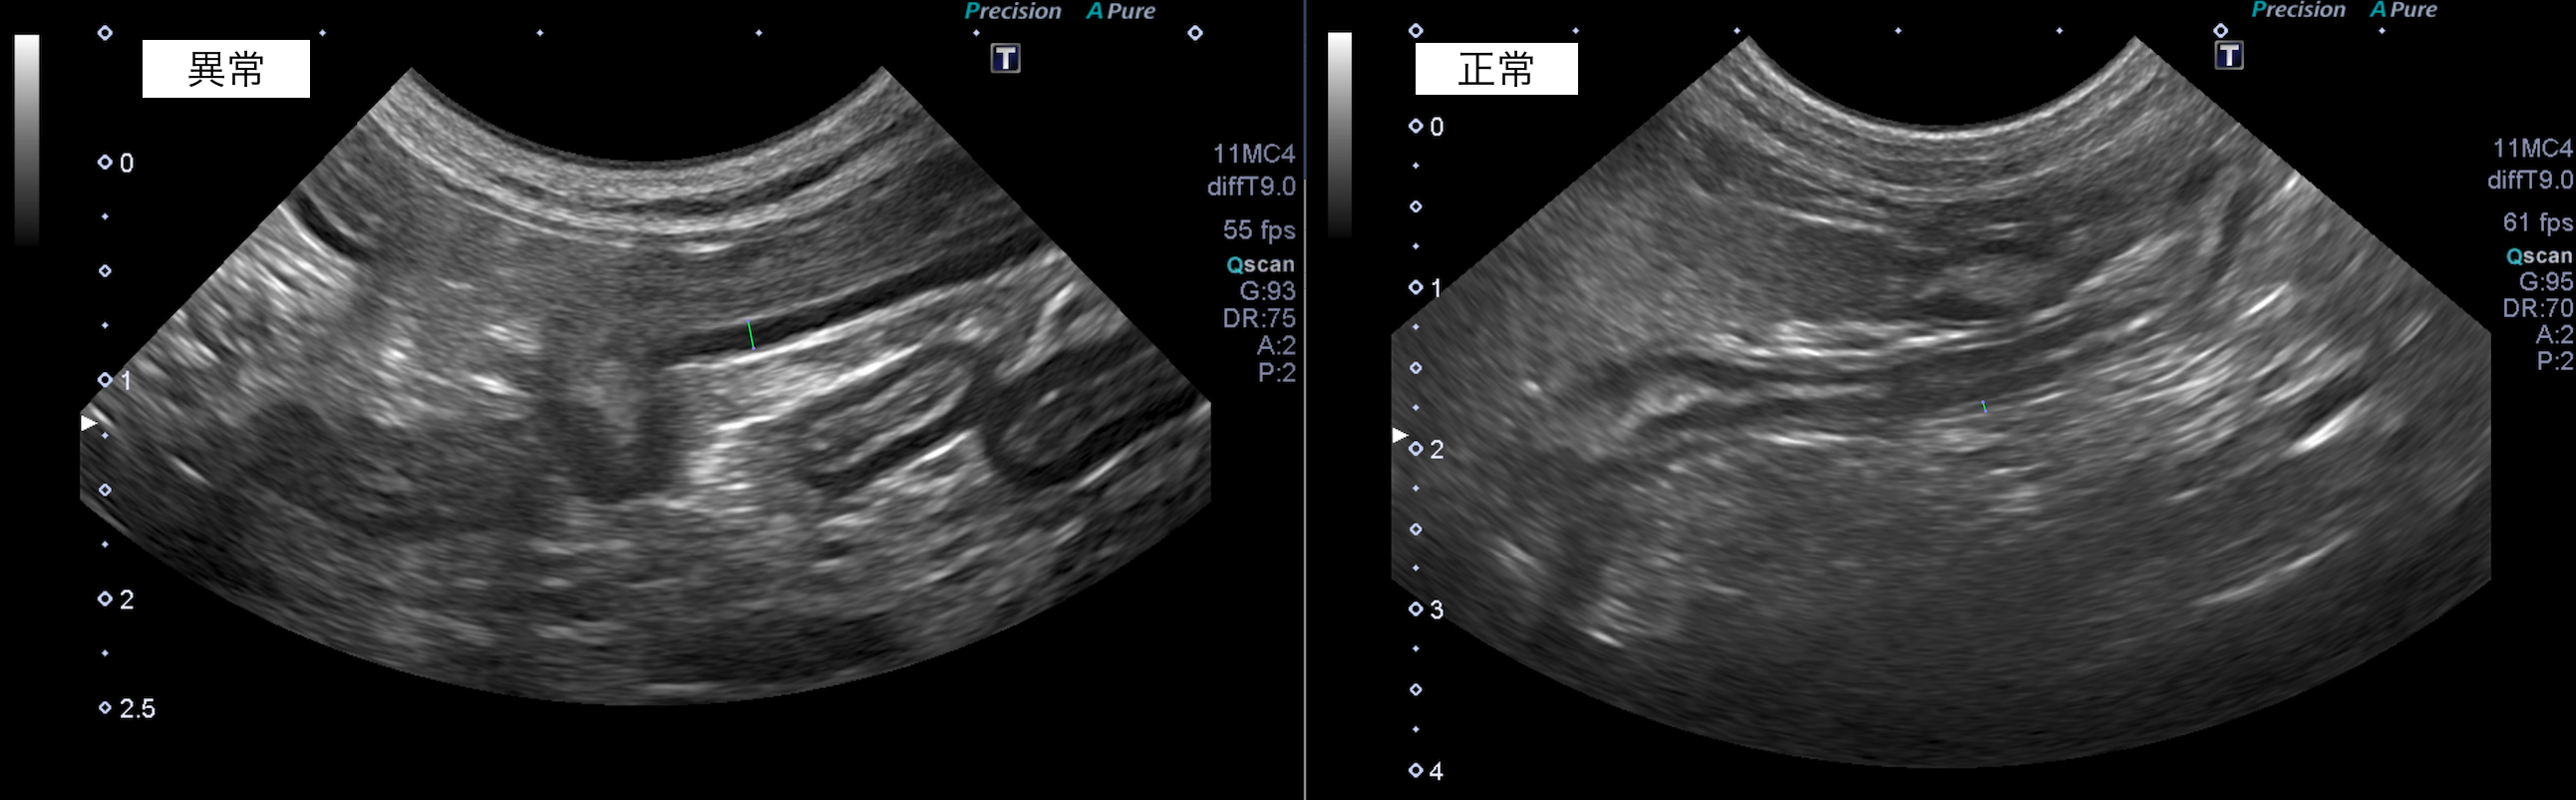

超音波検査で消化管の異常を把握することは可能ですが、内視鏡検査や開腹での生検を行わないと確定診断は行えません。

超音波検査では、消化管の構造の一部肥厚が認められました。

また超音波検査でも粘膜の肥厚は改善傾向です。